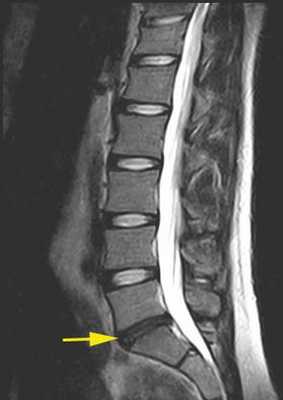

Пациентка Н., 69 лет, поступила в апреле 2016 г. в отделение онкоортопедии МНИОИ им. П.А. Герцена с диагнозом хондросаркома позвонка LII T3N0M0 G1 III стадии. Пациентка самостоятельно не передвигалась из-за выраженного болевого синдрома в проекции поясничного отдела позвоночника. 3 балла по ECOG, 50 баллов по шкале Карновского и 3 балла по Watkins. Парапарез нижних конечностей до 2 баллов. В апреле 2016 г. 1-м этапом выполнена декомпрессивная ламинэктомия позвонков LI—II с задней стабилизацией на уровне позвонков ThXII—LIII. Послеоперационный период без осложнений. Далее в мае того же года выполнен 2-й этап хирургического лечения: корпорэктомия позвонков LI—II с эндопротезированием тел позвонков телескопическим эндопротезом (рис. 3). Пациентка выписана на 9-е сутки после операции, передвигалась самостоятельно без дополнительных средств опоры (1 балл по ECOG, 80 баллов по шкале Карновского, 1 балл по шкале Watkins), рекомендован динамический контроль онколога по месту жительства.

Рис. 3. МРТ-картина до хирургического лечения (а). Тело позвонка LII с признаками деструкции, структура его представлена опухолевой массой размером 87×57×67 мм. Интраоперационная фотография (б), боковой доступ. Установленный телескопический эндопротез тел позвонков LI—II c боковой фиксирующей пластиной. Послеоперационная рентгенограмма поясничного отдела позвоночника (в). Металлоконструкция установлена корректно. Исследование выполнено на 1-е сутки после хирургического лечения.